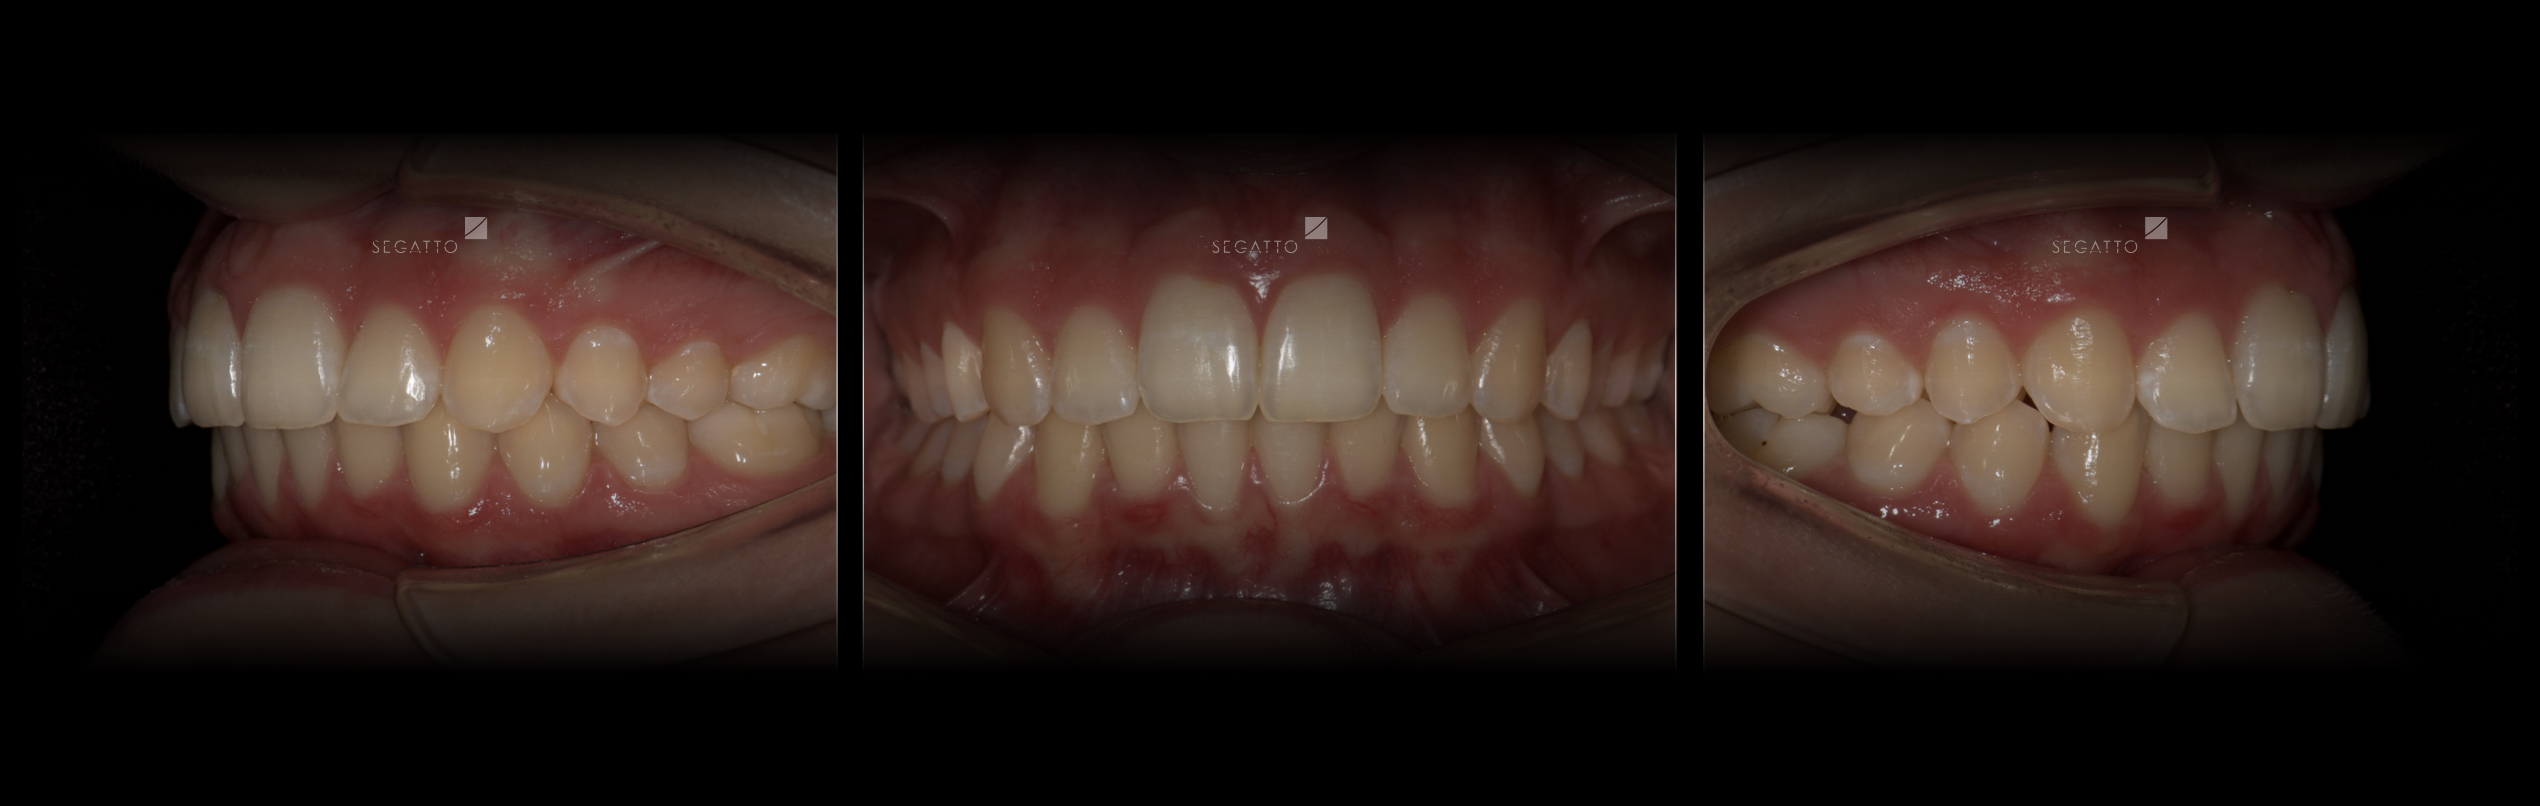

Orthodontics

Cases